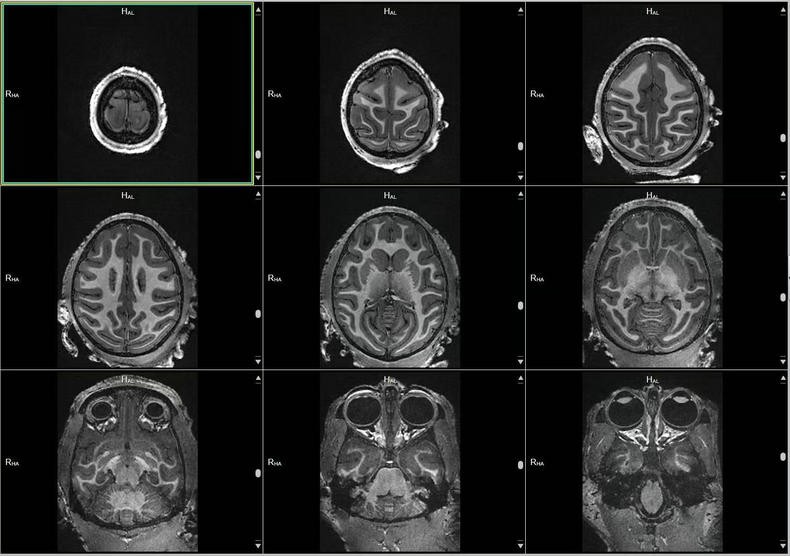

- 关键词:2023-2025年,猕猴,脑部磁共振,3D影像,T1w序列,T2w序列

预定本数据集为2023-2025年对25只20岁以上老年健康雌性猕猴的脑部磁共振扫描收集的数据,主要包括T1w序列和T2w序列影像(3D影像),对于神经学、心理学、行为学等多个相关学科的研究提供丰富的脑数据支撑。

a.物种:猕猴

b.实验动物信息

样本数量:25只

年龄分布:20岁以上

重量分布:4-16kg

性别分布:雌性25只

c.扫描仪规格

扫描仪类型:联影uMRNX 3.0T磁共振扫描仪器

线圈:12通道猕猴专用头线圈

d.扫描程序

动物福利伦理:由中国科学院昆明动物研究所实验动物福利伦理委员会批准。

动物护理和饲养:中国科学院昆明动物研究所实验动物中心

麻醉程序:阿托品(0.5mg/ml)-氯胺酮(0.05mg/ml)-丙泊酚(2mg/ml),阿托品和氯胺酮之间间5-10分钟,氯胺酮和丙泊酚之间间隔5-10分钟。

麻醉和扫描间隔时间:从阿托品算起,大约25分钟,从氯胺酮算起大约15分钟。

扫描体位:仰卧头先进

原始数据,未经加工处理。

数据采集使用联影uMRNX 3.0T磁共振成像仪器,该设备质量符合国家相关标准,所有设备操作者均接受上岗培训,以确保获得合格的高清晰度图像。